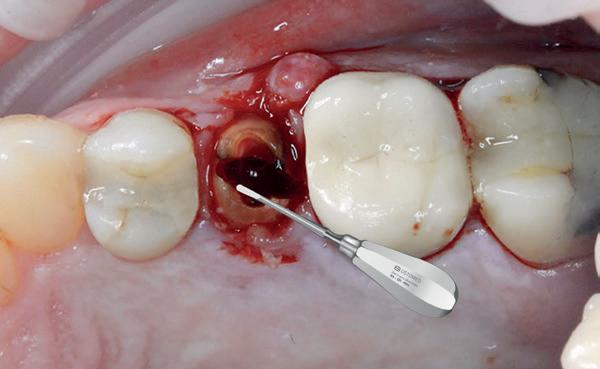

2. Decapiteren van het element en splitsen van de wortels.

3. Verwijderen van de radices.

4. Curettage en spoelen met een zoutoplossing.

5. Het ridge preservation protocol waarbij we proberen zoveel moge-

lijk bot te behouden met behulp van een xenograft.

6. De tijdelijke pontic, waarbij gebruikgemaakt wordt van de eigen afgebroken kroon en wat composiet. 7-10. Een full thickness flap osteotomie met hand plaatsing van een MegaGen AnyRidge Implantaat volgens protocol resulteerde in een

De implantaatplaatsing en de beslissende fout (afbeelding 1-13)

De extractie verliep voorspoedig, waarbij ik zoals al-

primaire stabiliteit van 60 Ncm.

11. Röntgenfoto ter controle van de plaatsing en de angulaire. Dit bone-level implantaat werd 4 mm onder de weke delen geplaatst.

12. Direct post-op. Een direct geplaatste tijdelijke kroon. Vastgezet met een torque van 20 Ncm en gehecht met prolene 5/0.

tijd probeerde de buccale botlamel intact te houden. Dit is cruciaal voor latere botbehoud en implantaatplaatsing. Na curettage en spoelen van de alveole beoordeelde ik de situatie opnieuw: de botcondities leken gunstig voor een immediaat implantaat.

Hier begon echter de cruciale fout in mijn klinisch besluitvormingsproces. In mijn streven naar maximale primaire stabiliteit - wetende dat immediaat belasten enkel mogelijk is bij hoge stabiliteit -on-

13. Röntgenfoto ter controle van de pasvorm van de direct geplaatste tijdelijke kroon.

14-16. Patiënt presenteerde zich met een forse zwelling en botverlies rondom het implantaat.

17. Verwijderen van de tijdelijke kroon.

18. Explantatie van het implantaat.

19. Curettage van de alveole in combinatie met curettage totdat er geen exsudaat meer was.

derprepareerde ik de osteotomie. Dit betekende dat ik een iets te smal implantaatbed creëerde, in de hoop dat het implantaat stevig in het bot verankerd zou worden.